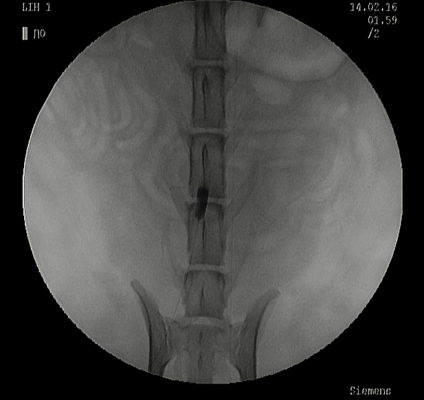

心血管造影検査(循環器科)

‣心血管造影検査について

心疾患の多くは心エコー検査で非侵襲的に診断が可能であるものの、非侵襲的な心臓検査のみでは診断が下せなかった場合、もしくは先天性心疾患(動脈管開存症ならびに肺動脈弁狭窄症)の診断・治療を行う際に追加検査として実施します。

‣心血管造影検査の方法

全身麻酔下にて透視X線装置と特殊なカテーテルを使用して検査を実施します。

‣当院での症例紹介

正常:右心系

正常:左心系

動静脈瘻

動脈管開存症